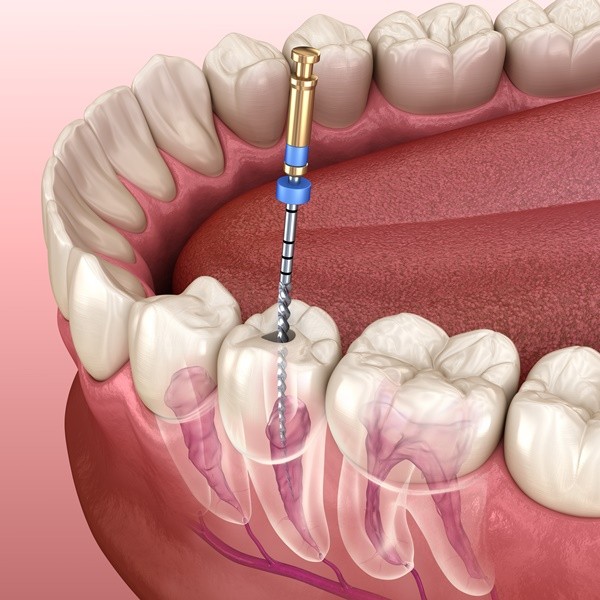

ROOT CANAL

A root canal is a treatment wherein the dental pulp of a tooth is cleaned out. The space inside of the tooth is disinfected and then filled and sealed, thereby saving a badly damaged or infected tooth. Common reasons why dental pulp is in need of repair are a cracked tooth, a deep cavity, repeated dental treatment on the tooth or trauma. The process is called a "root canal" because it involves the cleaning of the canals inside the tooth's root.